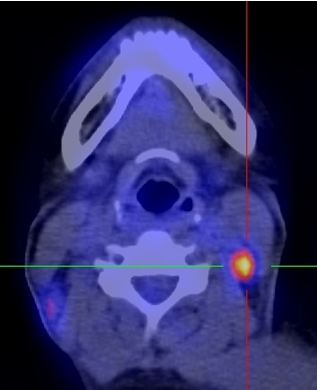

Trên lâm sàng và CT không phát hiện được hạch cổ. Nên kế hoạch điều trị là: xạ trị đơn thuần, với tổng liều vào u vòm là 70 Gy, vào vùng cổ 2 bên 50 Gy.

Trên PET/CT phát hiện hạch di căn vùng cổ trái, nên đã thay đổi giai đoạn bệnh, và làm thay đổi kế hoạch điều trị: xạ trị kết hợp hóa chất, tổng liều vào u vòm: 70Gy, liều vào hạch vùng cổ trái: 70Gy, dự phòng vùng cổ phải: 50Gy.

Hình 2: Hình ảnh PET/CT phát hiện thêm được hạch cổ phải, CT bỏ sót không thấy

Do PET/CT có độ nhạy và độ đặc hiệu cao hơn nhiều so với CT (khoảng 30% hạch cổ di căn mà lâm sàng và CT bỏ sót), nên đã làm thay đổi giai đoạn bệnh và từ đó làm thay đổi thái độ điều trị cho người bệnh.